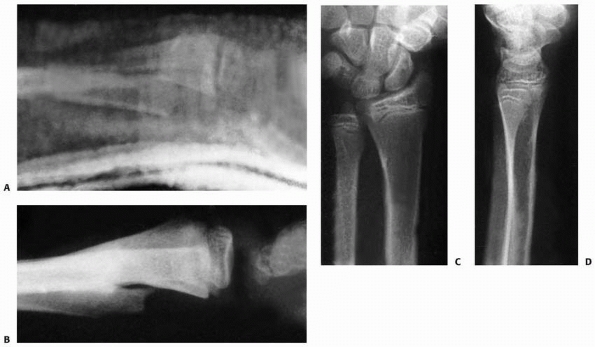

![]() |

FIGURE 9-16 A. AP and lateral radiographs of severely displaced Salter-Harris type II fracture of the distal radius. B. Closed reduction shows marked improvement but not anatomic reduction. The cast had to be bivalved due to excessive swelling. (continues)

FIGURE 9-16 (continued) C. Unfortunately, the patient lost reduction after a new fiberglass cast was applied. D. Out-of cast-radiographs show a healed malunion in a similar position to the prereduction radiographs.